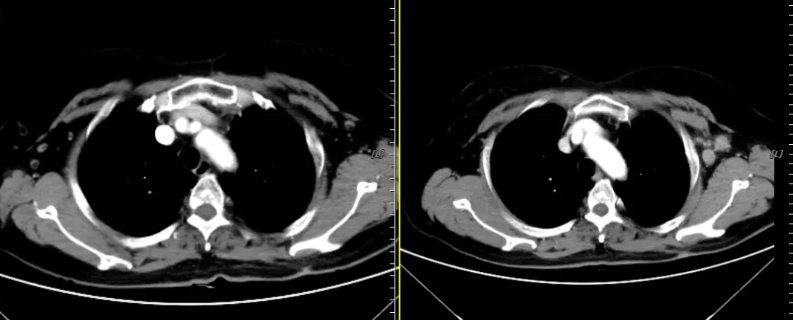

2022年5月17日查颈部、胸部增强CT:食管中下段管壁稍增厚,较前大致相仿,左侧颈部、左侧胸廓入口处及左侧腋窝多发肿大淋巴结影,左侧胸廓入口处淋巴结较前大致相仿,余较前新增,考虑转移。疗效评价为疾病进展(PD)。

图7 左侧颈部、左侧胸廓入口、左侧腋窝CT示多发肿大淋巴结(2022-5-17)

图9 CT评估示病灶明显缩小(左:2022-7-17;右:2022-12-6)